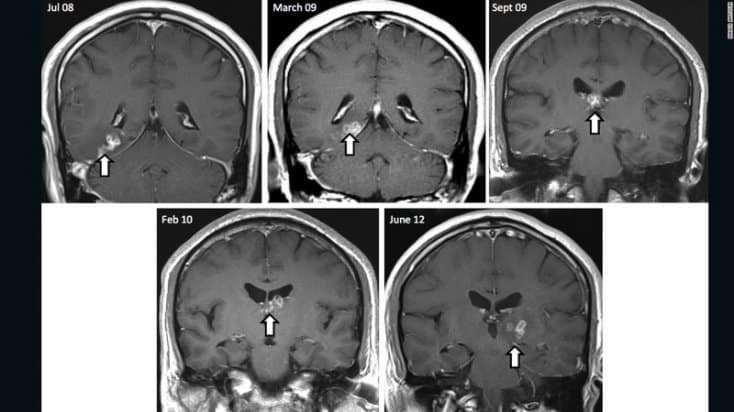

A médica grega Dra. Effrosyni Gkrania-Klotsas relembra um caso envolvendo um homem em 2013. Após uma viagem pela China, o paciente foi diagnosticado com o parasita Spirometra erinaceieuropaei. “Ele se mudou de um lado do cérebro para o outro. E poucas coisas se movem no cérebro”, comentou a doutora.

A presença do verme fazia com que ele sofresse com dores de cabeça agudas, fraquezas musculares e até mesmo com convulsões. E a infecção foi contraída após o consumo de carne de porco no país, de acordo com o especialistas que o examinaram.